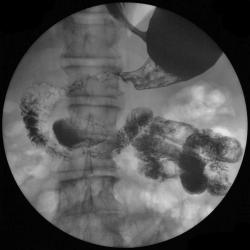

А это тоже дивертикул????

Изображение

Случай интересный, в плане сочетания дивертикула пищевода и тонкого кишечника с органикой желудка.

Это тоже дивертикул???

или это два дивертикула, которые наложились друг - на друга?